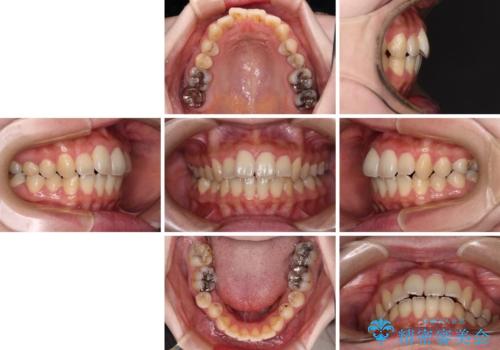

- 捻れた前歯が飛び出しており、口が閉じにくいとのことで来院された患者様です。

出っ歯というわけではないものの、前歯の捻転により口唇が押し出されている状態でした。

親知らずを抜去し、歯列全体を後方に移動させつつ、IPR(歯と歯の間を削る)でスペースを獲得し、インビザラインを用いて叢生を解消しながら前歯の突出を改善することとしました。

インビザラインは、患者様の協力無しには成立しない治療ですが、しっかりと装着時間を遵守してくださり、1年弱で治療を終えることができました。